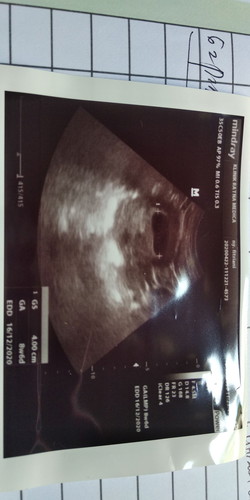

usia kehamilan 9 minggu di usg BO. harus gimana ya.

Dokter langsung bilanh hamil BO dan disuruh kuret. Sedih rasanya